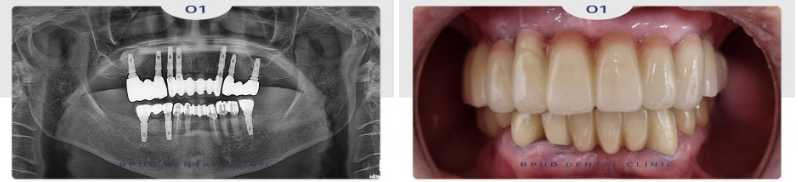

24.08.03

정기 검진 차 내원해 주셨을 때도

너무너무 편하게 잘 사용하고 있다고

해주셨는데요.

앞으로도 꾸준한 부평치과 정기 검진을

약속해 주셨습니다!